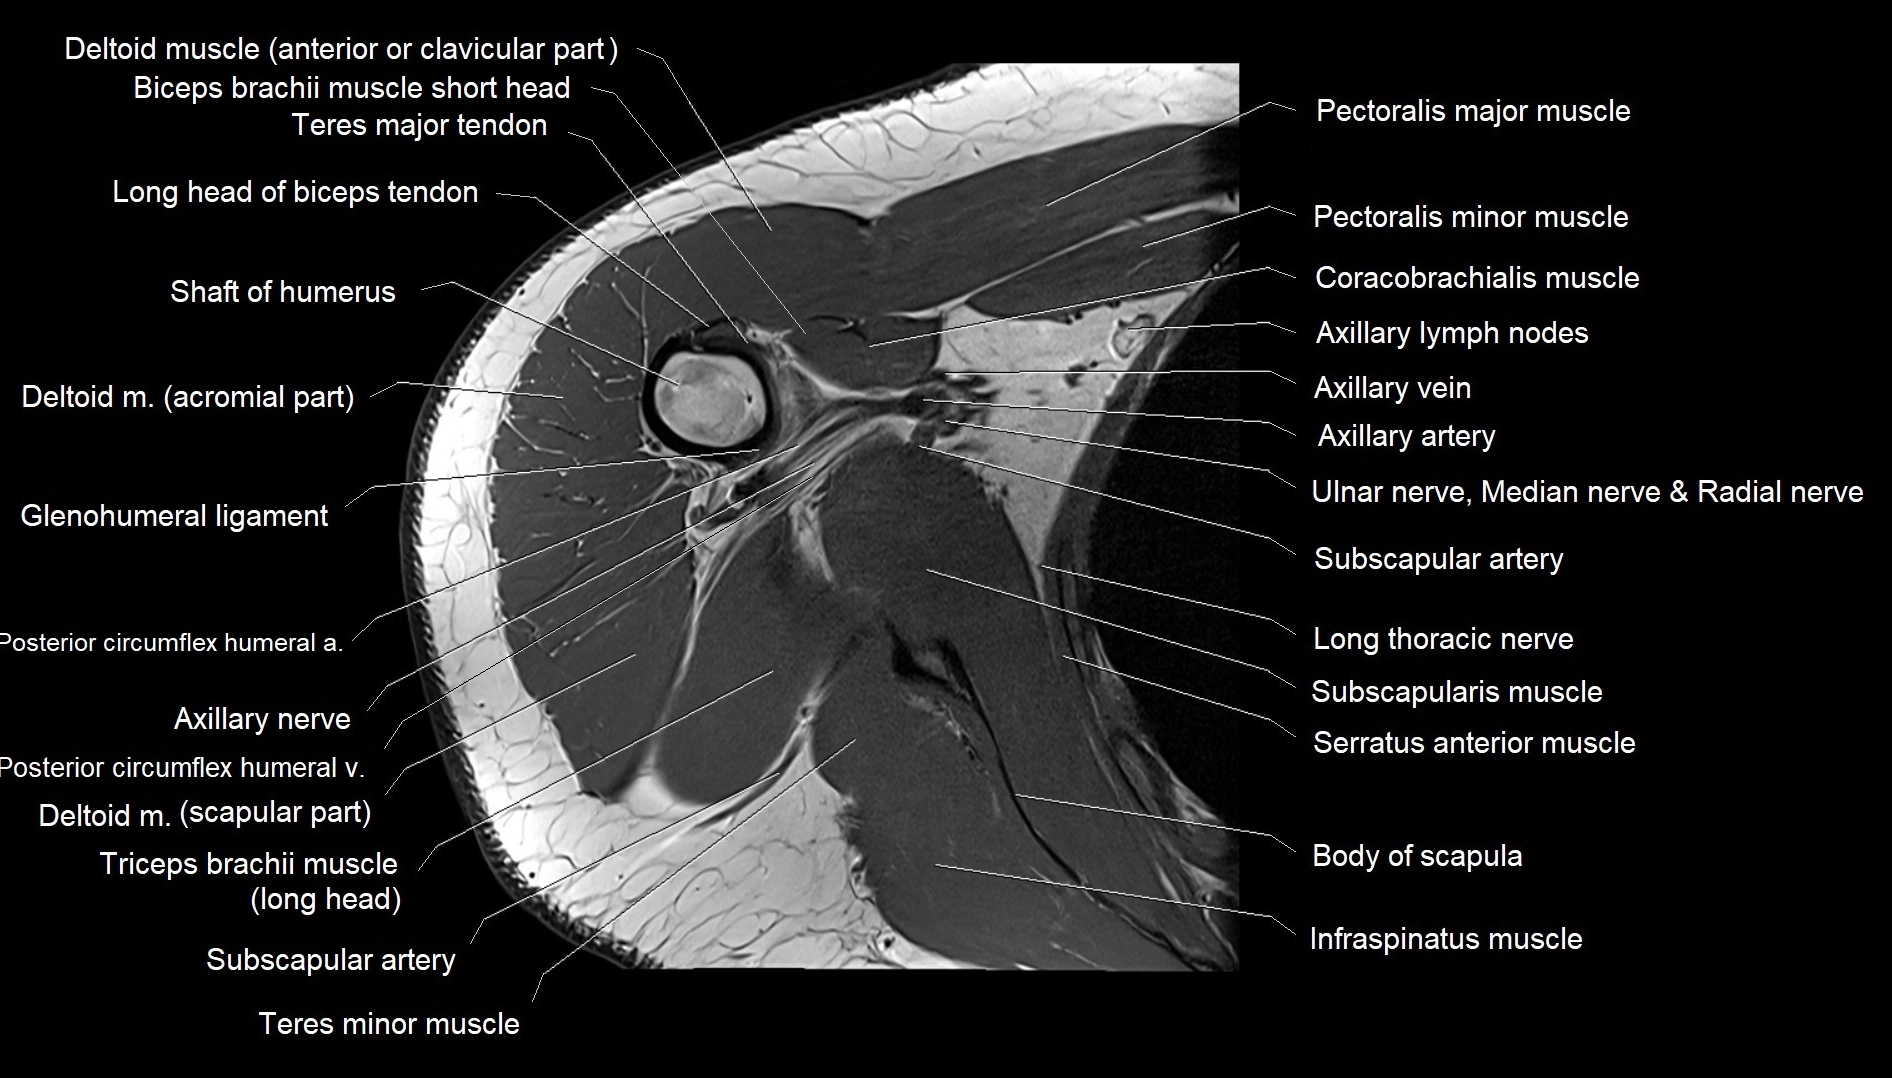

MRI images

image